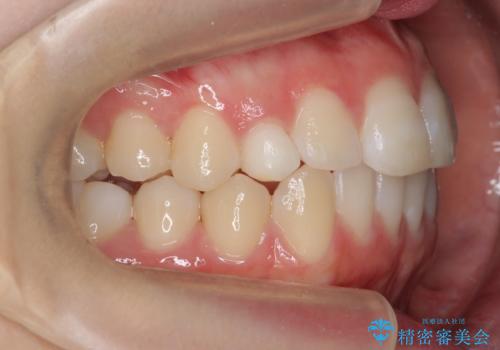

前歯のがたつき 乳歯を抜かずに矯正

- 前歯のがたつきを主訴に来院。

右上に乳歯が残っていましたが、後継永久歯がないため、抜かずに矯正しました。

乳歯の部分が反対咬合でしたが、歯列矯正で被蓋が改善するように移動させました。

右上の乳歯は移動させましたが、幸い矯正後にぐらつくこともなく、そのまま抜けるまで使うことにしました。